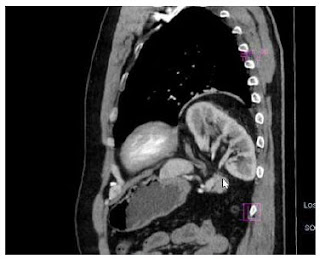

Procurou atendimento devido a persistência e agravamento dos sintomas. Após primeiro atendimento, realizou-se cateterismo nasogástrico, com drenagem de secreção borrácea, apesar da dificuldade de progressão do cateter. Trouxe consigo tomografia computadorizada (TC) de abdome e pelve do ano anterior que mostrava hérnia diafragmática em cúpula frênica à esquerda, com todo estômago herniado para o tórax. Solicitado endoscopia digestiva alta (EDA), nova TC de tórax, abdome e pelve, além de revisão laboratorial. A EDA diagnosticou sinais de esofagite erosiva grau D de Los Angeles, além de provável hérnia hiatal, com estômago predominantemente intratorácico, com alteração do seu eixo, sugerindo volvo gástrico. A TC replicava os resultados da EDA, demonstrando rotação gástrica no eixo mesenteroaxial, condicionando semiobstrução (Figura 1).

Figura 1. Reconstrução coronal de tomografia de tórax demonstrando estômago (E) presente dentro do tórax. Notar que o mesmo atravessa o diafragma (D) e apresenta linha (*) não preenchida pelo conteúdo, característica do volvo gástrico